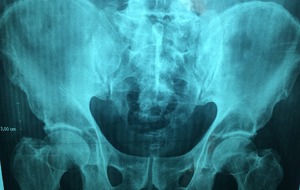

Общая рентгенодиагностика (Рентген)

Рентгеновское отделение оснащено современным цифровым оборудованием, которое позволяет получать диагностические изображения высокого качества с низкой лучевой нагрузкой